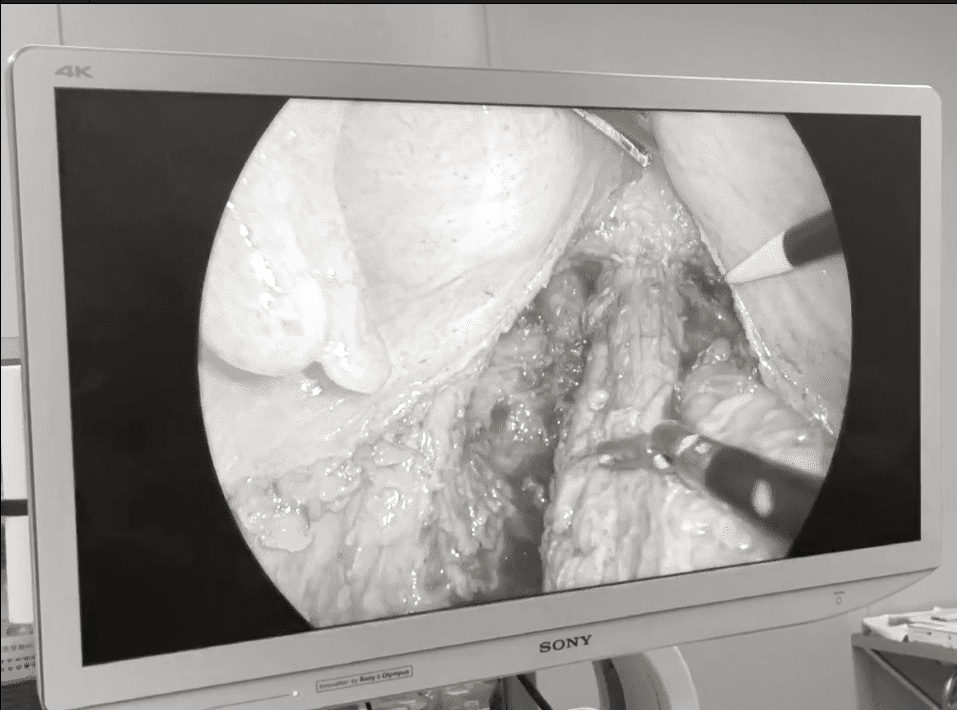

根据两位患者直肠癌病理性质、临床分期,以及肛门括约肌功能,普外科团队经过严谨地讨论,确定了个性化的手术方案,并由韩猛虎副主任主刀择期为白大爷实施了腹腔镜下超低位直肠癌TME+ISR术+回肠暂时预防性造口术;为宋阿姨实施了腹腔镜下超低位直肠癌TME+ISR术+回肠造口术。手术在保障切缘组织病理阴性的同时,达到了肿瘤根 治的目的,成功保住了两位患者的肛门和肛门功能。

普外科韩猛虎副主任说:“该类手术对术者的微创手术技能要求极高,是一项极限保肛技术。”据他介绍,经内外括约肌间切除术(ISR)保肛技术是建立在全直肠系膜切除(TME)基础上的极限直肠癌保肛手术,能通过切除部分或全部肛门内括约肌,以获取足够的远端切缘,在提高低位直肠癌保肛率的同时,降低复发率。